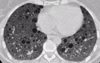

Qué patrón presenta ?

Patrón panal de abeja subpleural ( " simetrico ") NIU ( FPI )

Criterios dx fibrosis pulmonar idiopática

Patrón reticular Afectación subpleural y basal TCAR panal de abeja NO: vidrio esmerilado, micronodulos, quistes, mosaico, consolidación